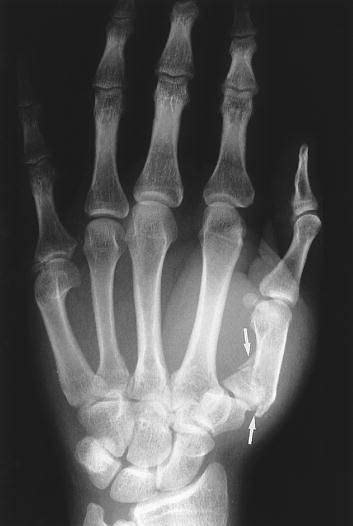

(8)Bennett 骨折

第一掌骨基底部关节内骨折伴脱位。